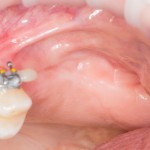

Молодой человек пришел ко мне. Вроде как ситуация неплохая:

1  2

На втором снимке видны рубцы от первой операции, но это мелочи. Ширина альвеолярного гребня, на первый взгляд, тоже не айс, но это легко поправимо.